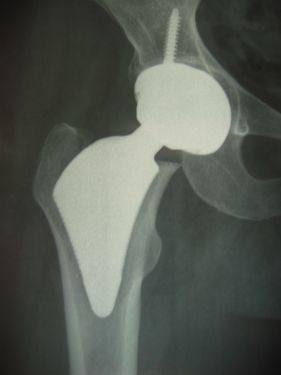

Changement de prothèse :

093   094 IMG 0229 IMG 0231   IMG 1157